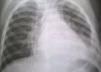

Human parechoviruses (HPeV), previously designated as echovirus 22 and 23, belong to the Parechovirus genus within the Picornaviridae family and has been designated HPeV 1 and 2 respectively.1 The HPeV genome organization and disease spectrum are similar to other viruses in the Picornaviridae family. HPeV have been frequently associated with respiratory and gastrointestinal diseases in children and severe disease in neonates that includes sepsis, meningitis, encephalitis, and hepatitis.2 In Brazil, HPeV type 8 was first reported in a gastroenteritis outbreak, where 35 stool samples were analyzed and 16.1% were HPeV positive.3 Highlighting HPeV as etiology of respiratory infection, the authors report the case of a 2-year-old girl with signs and symptoms of sepsis-like illness which progressed to sepsis with pulmonary focus. She was admitted to the pediatric emergency unit in a tertiary care hospital in Southern Brazil, with previous history of rhinorrhea, otorrhea and fever for seven days, and dry cough, poor food acceptance and emesis with grunting episodes in the three days prior to admission. Previously, the patient had two hospitalizations for pneumonia at the age of eight and 15 months. The mother reported meningitis outbreak at the patient's daycare 15 days before, and the child had the vaccination protocol updated. Upon admission, the patient weighed 13kg, had tachycardia (175beats/min) and tachypnea (33breaths/min), was in poor general condition, whining, pale, sleepy, with reduced vesicular murmur, fine crackles and dullness to percussion of left pulmonary lower medium-third. The lung ultrasound showed a small pleural effusion of 0.5cm thick, with no need of drainage. The patient progressed with respiratory insufficiency, altered consciousness level and septic shock requiring ICU monitoring and mechanical ventilation and her oxygen saturation was 91%. The patient had hemodynamic instability, requiring vasoactive drugs, metabolic acidosis and altered renal function. X-rays showed an acute respiratory distress syndrome (ARDS) pattern (Fig. 1), with bronchopneumonia and pulmonary edema; progressed with decreased urine output and worsening of urea and creatinine levels compared to the admission, which was managed with plasma, albumin and furosemide administration. She had a favorable outcome, and was discharged eight days after the admission. Microbiological investigation was negative for bacteria on blood and respiratory secretion. Respiratory viruses were surveyed in nasopharyngeal aspirates (NPA) using a PCR multiplex method (RV 15, Seegene®, South Korea), which detects respiratory syncytial virus A and B, adenovirus, influenza A and B, parainfluenza 1, 2, 3 and 4, human metapneumovirus, coronavirus OC43 and 229, human rhinovirus A, B and C that resulted negative. By molecular methods a conventional RT-PCR, to the 5′NCR as a target, was performed in NPA and detected HPeV, which was confirmed by nucleotide sequence method (Fig. 2).1 To our knowledge, this is the first report of HPeV circulation in south Brazil. Currently, 16 types of HPeV are recognized and reported mainly in patients under five years old. HPeV have a worldwide distribution and have been reported in many clinical conditions such as gastroenteritis, respiratory infections, neonatal sepsis, various and severe CNS diseases, including paralysis, meningitis and encephalitis. Each condition has been associated with different HPeV types.2 Respiratory symptoms, have been frequently reported in children with HPeV infections. Two recent studies investigating the involvement of HPeV in respiratory diseases detected HPeV1, HPeV3, and less frequently HPeV 4, 5 and 6 in children below five years old. However, these studies report low frequency of detection and high rate of co-infection with other respiratory viruses, hence preventing the elucidation of the role of these viruses in respiratory infections.1,4 Blood culture, considered the gold standard for neonatal infection diagnosis, has poor sensitivity (8–73%) and will not detect all pathogens and very little is known about non-bacterial pathogens as a cause of late onset infection. Davis et al. (2015) described the detection of HPeV 1 in a group of preterm infants in neonatal intensive care. In the total group, 13% of infants had HPeV type 1 infection confirmed by PCR method.5 In recent years, viral community-acquired pneumonia (CAP) has been reported as a frequent microbial etiology in severe CAP. This is in part due to new diagnostic techniques that allow detecting old and new viruses, such as Middle East Respiratory Syndrome (MERS), one of these new viral diseases, which is caused by an RNA betacoronoravirus.4 Neonates and young children are more vulnerable to infections than older children or adults. In this context, HPeV is now recognized as an important agent for infectious diseases and currently has 16 identified genotypes. Each genotype is related to various clinical patterns and by molecular methods HPeV 1 and 3 are the most frequent types involved in many severe infectious.2 This study shows a case of sepsis with pulmonary focus associated to HPeV infection and should serve as a warning to the introduction of this investigation in the routine care of patients with severe respiratory infection, meningitis, gastroenteritis, or neonatal sepsis, promoting epidemiological and longitudinal analyses seeking to understand the dynamics of this virus circulation and its impact on children's health.